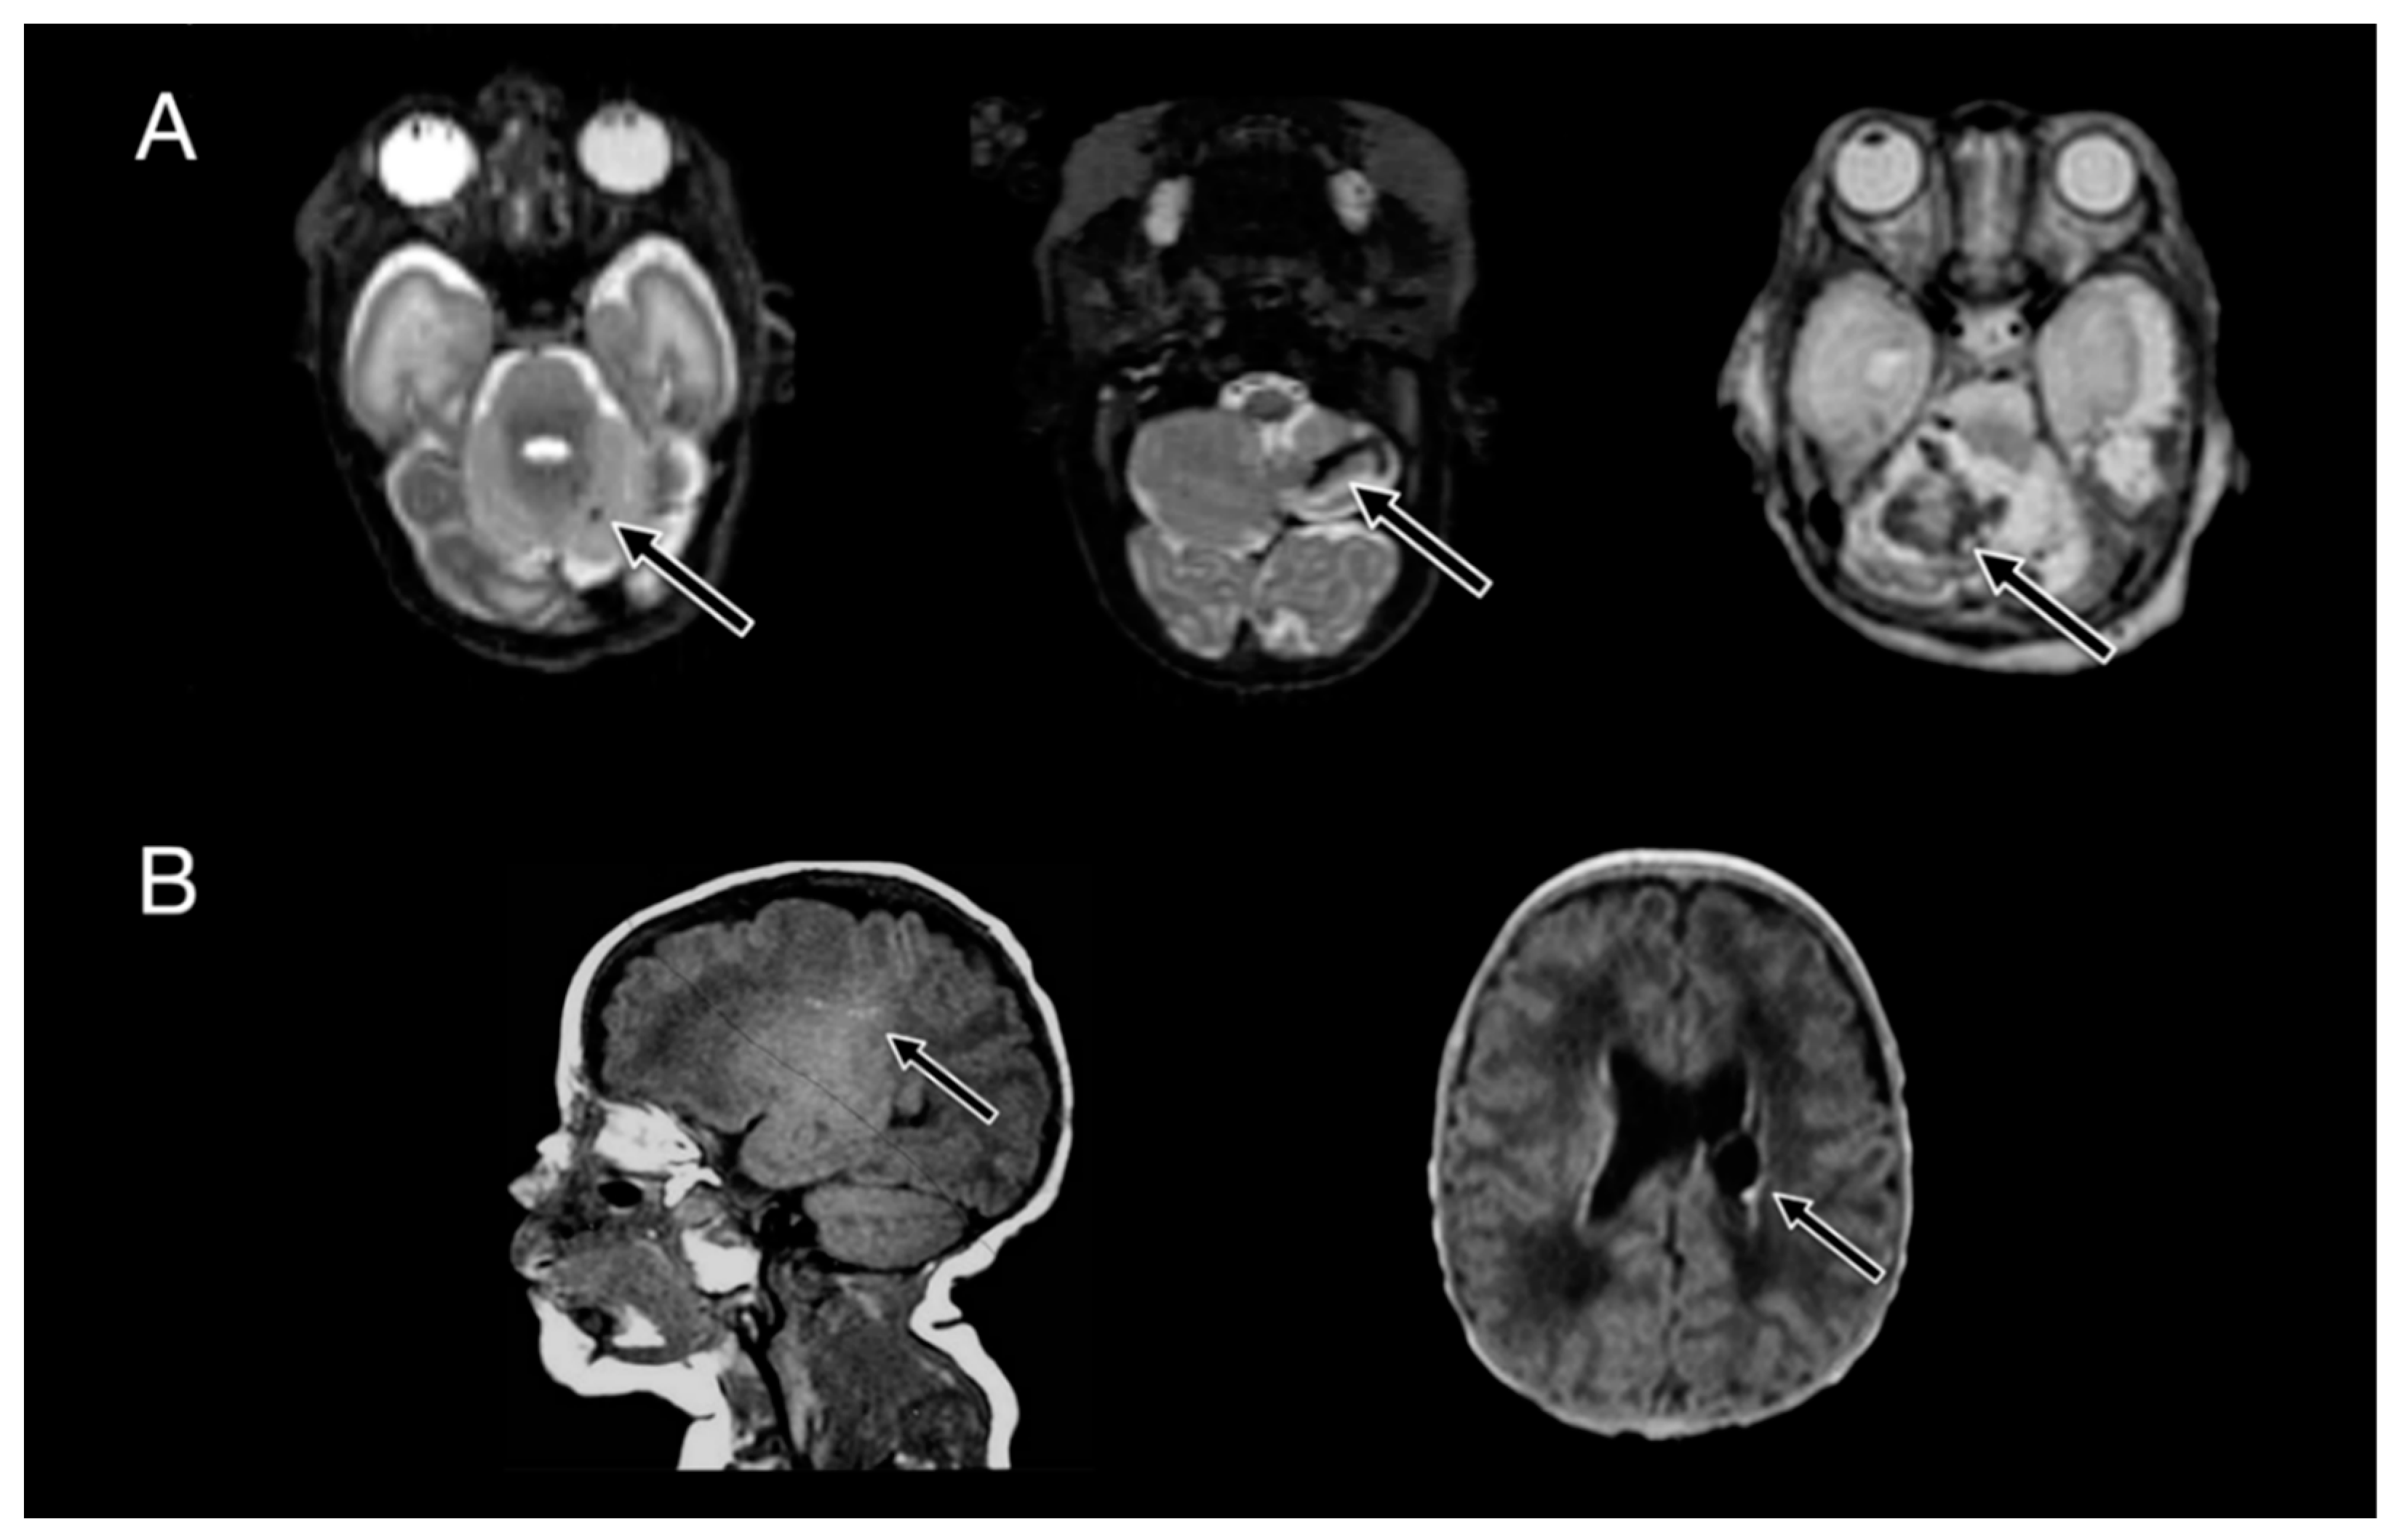

| Any IVH, n (%) | 55 (47) | 31 (82) | <0.01 * |

| Grade III/IV IVH, n (%) | 16 (14) | 23 (61) | <0.01 * |

| Any cerebellar hemorrhage, n (%) | 26 (22) | 15 (40) | 0.06 |

| Cerebellar hemorrhage size | |||

| Large, n (%) | 6 (5) | 8 (21) | 0.03 * |

| Small, n (%) | 12 (10) | 5 (13) | |

| Punctate, n (%) | 8 (7) | 2 (5) | |

| None, n (%) | 90 (78) | 23 (61) | |

| Bilateral cerebellar hemorrhage, n (%) | 15 (13) | 9 (24) | 0.12 |

| WMI (white matter injury) | |||

| Multiple punctate or cystic, n (%) | 15 (13) | 24 (63) | <0.01 * |

| Isolated punctate, n (%) | 22 (19) | 2 (5) | |

| None, n (%) | 79 (68) | 12 (32) | |

| Any brain injury, n (%) | 77 (66) | 34 (90) | <0.01 * |